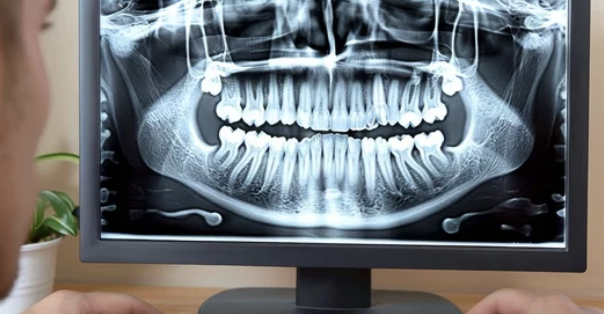

2. 치료 장비

- 최신의 3D 스캐너나 MRI, CT 등을 보유한 병원은 더 정확한 진단을 내릴 수 있습니다. 특히 교합 분석이나 턱관절의 움직임 분석이 가능한 장비가 있는지 확인하는 것이 좋습니다.